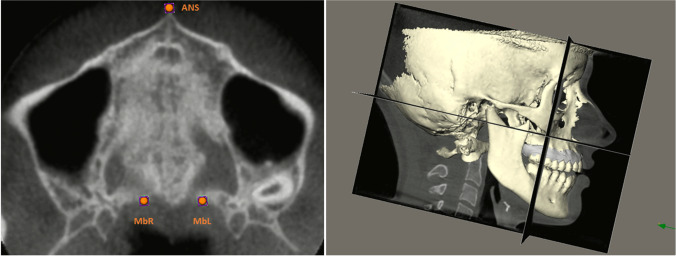

The stereolithography files from the IOSs and the Digital Imaging and Communications in Medicine files from the CBCT scans were fused using IPS CaseDesigner® software (KLS Martin Group, Tuttlingen, Germany), creating separate fusion models for T0 and T1 per patient. The created models were imported into Maxilim® software (Medicim NV, Mechelen, Belgium) and a 3D reference frame was set up as follows: the horizontal plane was defined as a plane passing through the anterior nasal spine (ANS-point) anteriorly and the left and right notch located on the posterior maxillary border (see: Fig. 5a); the midsagittal plane was constructed as a plane perpendicular to the horizontal plane passing through the ANS-point and the middle of the line between the left and right posterior maxillary notch; the vertical (coronal) plane was constructed perpendicular to the horizontal and midsagittal planes (see: Fig. 5b). After setting up the reference frame, the dental and skeletal landmarks were identified manually on each fusion model.

Fig. 5.

Orientation of the CBCT. (A: left) CBCT orientation of the horizontal plane defined by 3 landmarks: ANS-point, maxillary posterior border notch on the right (MbR), maxillary posterior border notch on the left (MbL). (B: right) CBCT orientation with 3D reference frame